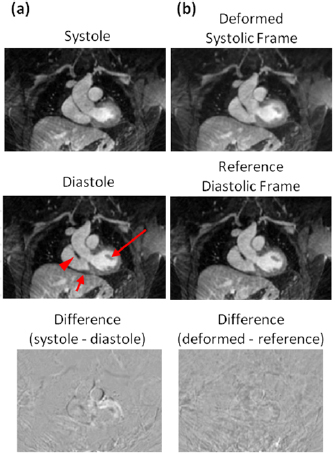

The efficacy of the MR-based motion modeling approach is demonstrated in figures 5 and 6. The four respiratory frames reconstructed by self-gated radial stack-of-stars MR are shown in figure 5. The level of the diaphragm can be seen to differ at inspiration and expiration as expected. MVFs derived by affine registration between frames, when applied to each frame, produce deformed images that align with the expiration reference frame. The fidelity of the transformation is shown by low residual errors in the difference images between the reference and transformed frames. Cardiac frames at systole and late-diastole are shown in figure 6. Morphological differences are evident, including the size of the ventricle, width of the aortic outflow tract, location of the papillary muscle, and shape of the right ventricular wall. The systolic frame, when transformed to the reference late-diastolic frame by non-rigid registration, shows good agreement with the reference. Difference images show structured spatial mismatch errors are resolved after transformation.

Standard image High-resolution imageFigure 6. Cardiac motion modeling based on MR data. Systolic and late-diastolic frames (a) after respiratory motion correction and gating based on recorded ECG triggers show morphological differences in the size of the ventricle, width of the aortic outflow tract, location of the papillary muscle (long arrow) and shape of the right ventricle wall (short arrow). In (b), the systolic frame after being deformed to the target reference late-diastolic frame shows morphological features matching those in the reference, including thickness of the right ventricle wall with the outflow tract (arrowhead). The difference image between systolic and late-diastolic frames shows clear structure (a); whereas this has been minimized in the difference between deformed frame and reference frame (b).